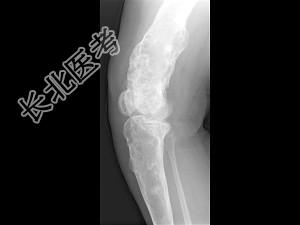

- 单项选择题女,42岁, 双下肢疼痛,结合图像, 最可能的诊断是 ( )

A、Paget病

B、内生软骨瘤

C、非骨化性纤维瘤

D、骨巨细胞瘤

E、骨纤维异常增殖症